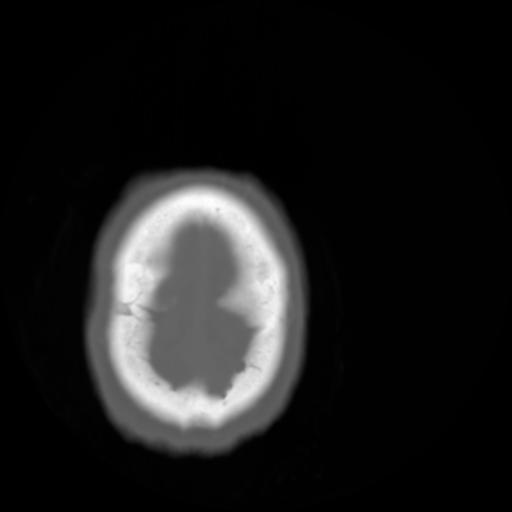

3 CEREBRO,,Axial,3.0,CEREBRO,,